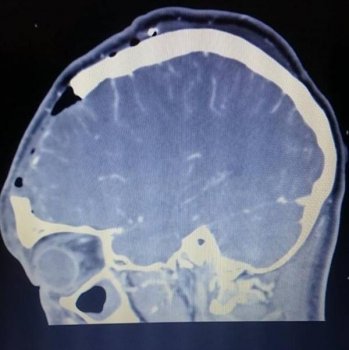

Im Jahre 2013 war ihr Geruchssinn immer noch nicht wieder zurückgekehrt. Nun dachten die Ärzte, dass es vielleicht doch etwas anderes sein könnte und ordneten ein CT von Tiffanys Schädel an. Dabei entdeckten sie eine Masse direkt zwischen ihren Augen. Nach einer Biopsie war klar, dass es keine Zyste war, die man einfach entwässern könnte. Dieser seltene Tumor benötigte eine schnelle Behandlung, da er nur durch sein Wachstum große Schäden an Gehirn und Körper verursachen könnte, berichtet der „Mirror“.

Die Ärzte im John Radcliffe Hospital in Oxford diagnostizierten ein Psammomatös Juvenile Ossifying Fibroma, ein gutartiger, aber seltener Tumor. In ihrem letzten Highschool Jahr unterzog sich Tiffany der Operation, um den Tumor zu entfernen. Sechs Stunden benötigten die Ärzte, den Tumor durch ihre Nase zu ziehen. Ein paar Tage nach der Operation war klar, dass etwas nicht stimmte, da Tiffany noch nicht wieder reagierte. Ihr Gehirn war stark angeschwollen und drückte gegen die Schädeldecke. Die Ärzte sahen sich gezwungen ein Stück des Schädels zu entfernen.

Trotz des fehlenden Stücks in ihrem Kopf, konnte Tiffany in ihr normales Leben zurückkehren, machte ihre Abschlussprüfungen und ging ihrem Nebenjob nach. Die Ärzte sagten Tiffany, dass ihr Stück Schädel von einem 3D-Drucker hergestellt wird. Das Dauerte jedoch über 3 Wochen, da es eine Verzögerung in der Firma gab. Das Schädelimplantat wurde nach CT- und MRT-Scans ihres Kopfes gefertigt. Nachdem die Ärzte sicher sein konnten, dass ihr Hirn nicht mehr anschwellen wird, setzten sie das Implantat aus Kalzium, Kunststoff und Titan ein.